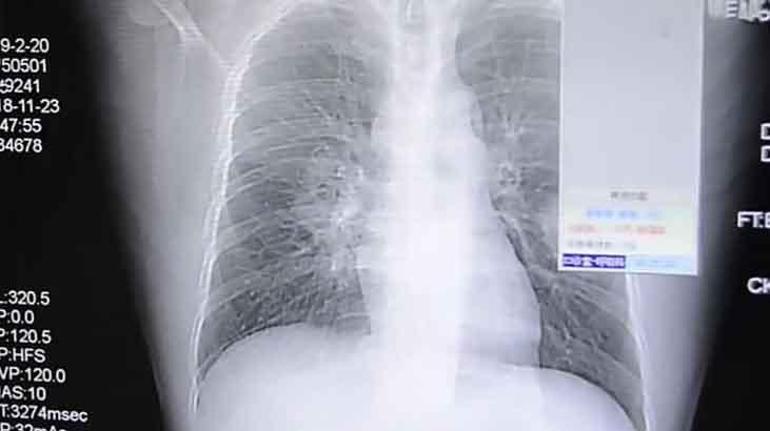

Betül Topaklı / Milliyet.com.tr – Her şey Çin’in güneybatısındaki Çongçing kentinde yaşayan bir adamın her gece öksürük krizi geçirmesiyle başladı. Yaşadığı bu olay üzerine hastaneye kaldırılan adama, hekimler çabucak müdahale etti. Yapılan bronkoskopi süreci sonucunda, orta yaşlı adamın sağ akciğerinde önemli bir enfeksiyon olduğu görüldü. Lakin bu olağan bir enfeksiyon değildi. Adamın, nemli yerlerde gelişen bir küf tipi olan Aspergillus’un neden olduğu bir çeşit akciğer rahatsızlığı olan Aspergilloz hastalığına yakalandığı ortaya çıktı. Tabipler, çabucak adamın bu hastalığa nasıl yakalandığını araştırmaya başladı. Hastayla yaptıkları konuşma sonrasında ise büyük bir şok yaşadılar. Çünkü adamın bu mantara yakalanma nedeni, çoraplarıydı. İşten geldikten sonra kirli çoraplarını koklayan adamın çoraplarını test eden tabipler, çorapların hastayı enfekte eden küfle birebir tipe sahip olduğunu tespit etti.

Ancak kelam konusu bu durum Çin’de yaşanan birinci olay değildi. 2018 yılında ülkenin güneydoğusundaki Zhangzhou kentinde yaşayan 37 yaşındaki bir adam da öksürük ve göğüs ağrısı şikayetiyle hastaneye kaldırıldı. Hasta, sıhhat görevlileriyle yaptığı görüşmede, ‘giydiği çorapların kokusuna bağımlı hale geldiğini’ söyledi. Onun da ayakkabılarında gelişen sporlardan kaynaklanan mantar akciğerinde enfeksiyona yol açmıştı.

Çin’in Çongçing kentinde yaşayan adam (sağdaki resimde) şiddetli bir öksürük krizi geçirdikten sonra hastaneye kaldırıldı.